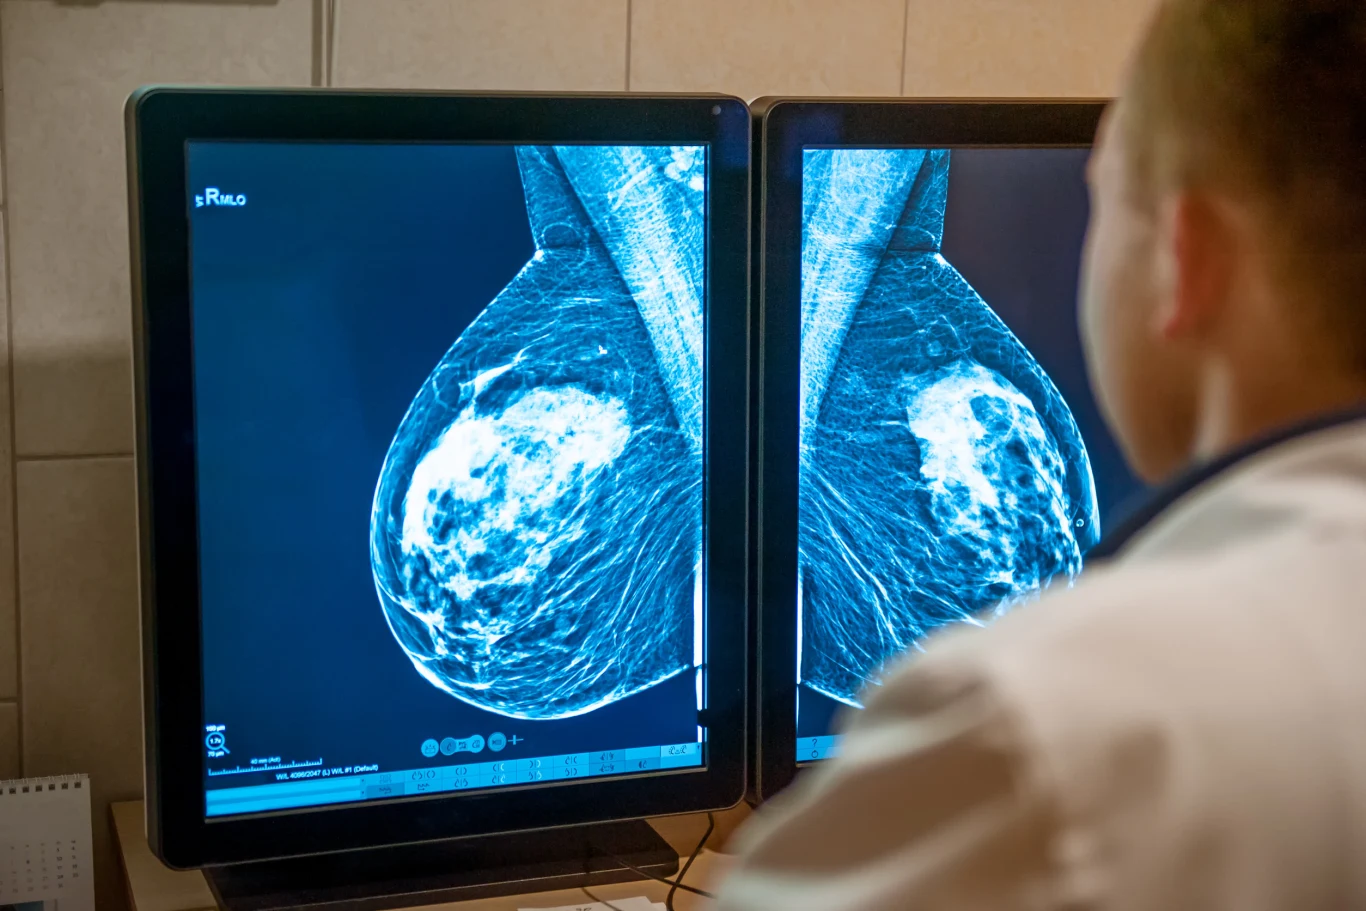

Najważniejsza różnica między mammografią a USG piersi - mammografia to radiologiczne badanie piersi (prześwietlenie rentgenowskie z użyciem niskiej dawki promieniowania), a USG piersi to badanie ultrasonograficzne, które wykorzystuje ultradźwięki.

Mammografia, tak jak USG piersi, potrafi wykazać nawet milimetrowe zmiany, których nie wyczujemy w badaniu palpacyjnym. Specjaliści podkreślają, że badanie to pozwala wcześnie wykryć ponad 90 proc. zmian nowotworowych (nawet dwa lata przed tym, jak pojawi się guz wyczuwalny w samobadaniu). W trakcie mammografii osoba przeprowadzająca badanie umieszcza pierś w odpowiedniej pozycji na płycie sprzętu. Potem dochodzi do uciskania gruczołu przez drugą płytę (ucisk stopniowo będzie się zwiększał). Niewielki ucisk jest konieczny do tego, by uwidocznić wszystkie tkanki piersi i zwyczajnie niczego nie przegapić. Taka pozycja pozwala także utrzymać pierś w jednej pozycji. W ten sposób zostanie zbadana każda z piersi, co nie trwa dłużej niż 15 minut (sam ucisk piersi trwa krócej niż 30 sekund). Niekiedy konieczne jest wstrzymanie oddechu lub zajęcie pozycji skośno-bocznej.

Mammografia to badanie, które powinno być wykonywane raz na dwa lata przez kobiety od 40. do 50. roku życia. Po 50-stce należy je wykonywać raz w roku. O badaniu tym powinny pamiętać osoby, u których w rodzinie wystąpiła mutacja genowa BRCA 1 lub BRCA 2 lub u których jedna z najbliższych członkiń rodziny miała nowotwór piersi lub jego podejrzenie. U mężczyzn mammografia również jest wykonywana.

Badanie mammograficzne w ramach NFZ można wykonać po okazaniu skierowania od specjalisty. Badanie jest bezpłatne dla kobiet w wieku 50-69 lat, które w ciągu ostatnich dwóch lat nie miały go wykonywanego. Wykonanie mammografii prywatnie to koszt ok. 100 zł. Wyniku nie otrzymuje się od razu - zazwyczaj po dwóch dniach.